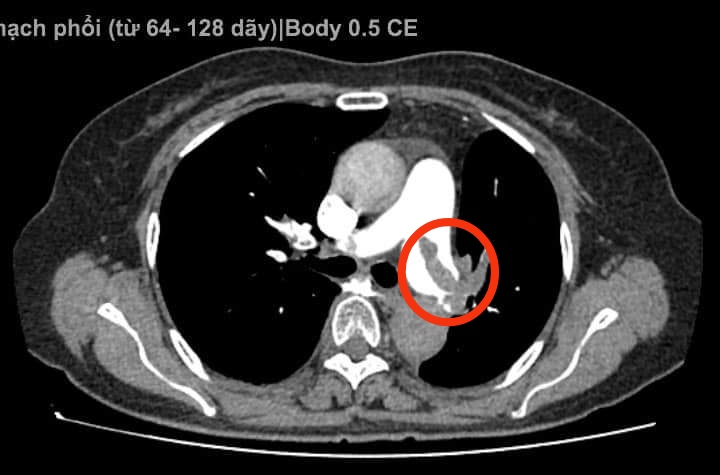

Qua thăm khám lâm sàng và điện tâm đồ, nghi ngờ bệnh nhân bị tắc động mạch phổi cấp, các bác sĩ đã ngay lập tức chỉ định thực hiện siêu âm tim thấy có huyết khối trong buồng tim phải, huyết khối trong động mạch phổi. Để chẩn đoán xác định, các bác sĩ tiếp tục chỉ định chụp cắt lớp vi tính động mạch phổi, kết quả cho thấy bệnh nhân bị tắc động mạch phổi cả 2 bên. Lúc này, diễn biến lâm sàng của bệnh nhân xấu hơn, đau ngực nhiều, khó thở, nhịp tim nhanh 115 lần/phút.

Hình ảnh tắc động mạch phổi trên phim chụp MSCT

Sau 5 ngày điều trị theo phác đồ, kết quả chụp MSCT động mạch phổi cho thấy huyết khối ở thân động mạch phổi đã hết, huyết khối ở hai nhánh lớn động mạch phổi đã giảm rất nhiều. Bệnh nhân đi lại, sinh hoạt bình thường và đã được ra viện ngày 19/10/2023.